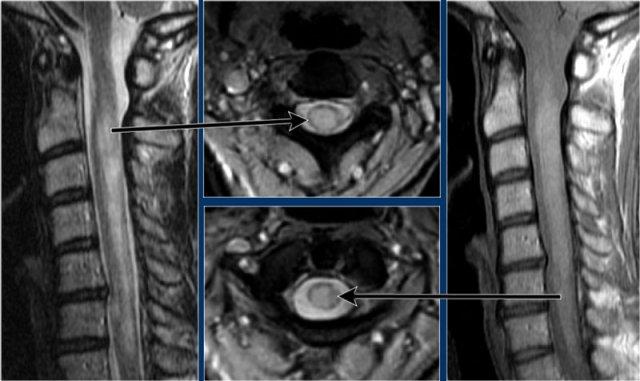

Đây là hình ảnh của một trường hợp điển hình.

Nhiều khi tiền sử lâm sàng rất hữu ích như trong trường hợp này.

Bệnh nhân nữ 24 tuổi có rối loạn thị giác một mắt, sau đó vài năm xuất hiện yếu và rối loạn cảm giác ở chi dưới và chi trên.

Hiện tại bệnh nhân đến khám vì rối loạn cảm giác ở cả hai chi dưới.

Vì vậy chúng ta đã nghĩ đến MS.

Trong tủy sống có một số tổn thương bờ rõ, nhưng cũng có một số tổn thương bờ không rõ, mờ nhạt.

Hình ảnh cắt ngang cho thấy vị trí ở phía lưng và hình dạng tam giác điển hình.

Tiếp tục xem các hình ảnh sau tiêm thuốc tương phản từ

Trên các hình ảnh sau tiêm thuốc tương phản từ, không thấy ngấm thuốc.

Các tổn thương MS hoạt động ở tủy sống có thể ngấm thuốc, nhưng không phổ biến như các tổn thương hoạt động ở não.

Khi phát hiện tổn thương ở tủy sống, việc chụp thêm não cũng rất hữu ích.

Đôi khi bệnh nhân chỉ được chỉ định chụp MRI cột sống và không có đủ thời gian để thực hiện toàn bộ khảo sát não.

Trong những trường hợp đó, hãy cân nhắc chỉ thực hiện chuỗi xung FLAIR mặt phẳng đứng dọc.

Tiếp tục xem các hình ảnh của não.

MRI não cho thấy các tổn thương quanh não thất và một tổn thương ở thể chai.

Các vị trí này rất đặc trưng cho MS.